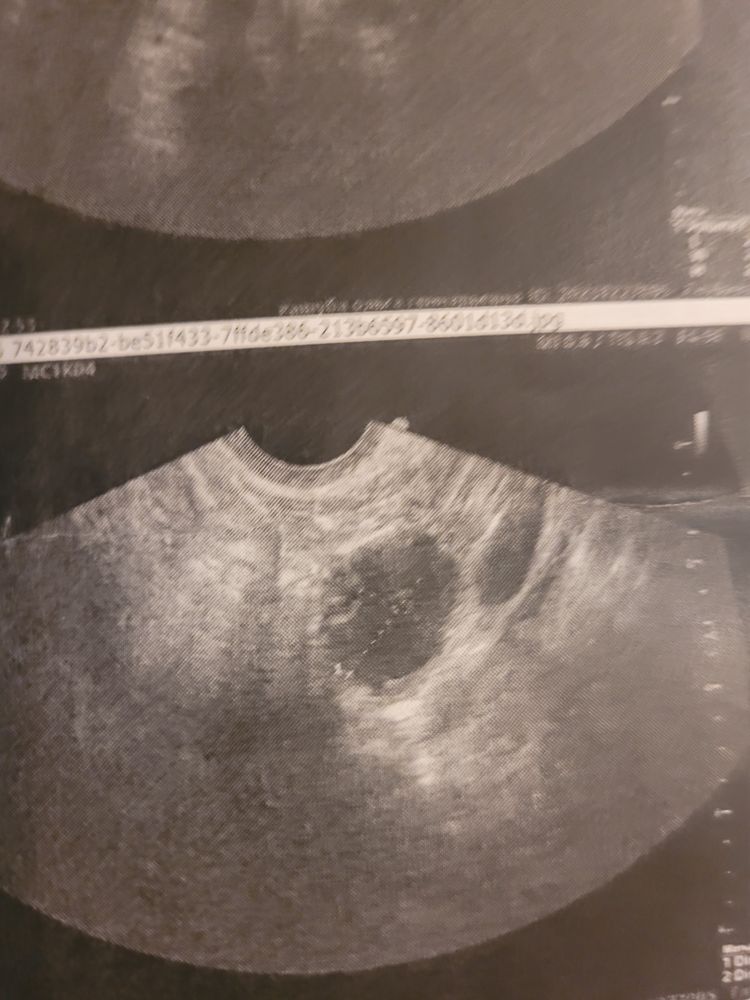

Всем привет. Сегодня была на узи нашли доминантный фолликул 25мм:21мм. Тест на овуляцию и узи прилагаю. Так не хочу кисту :( посмотрите плиз!

У вас же яйценосный бугорок видно даже )))) это значит что уже сегодня завтра фоликул выпустит яйцеклетку ☺️ удачи !

Череппааашка по имени Натааашка , у меня он был и на 20 мм. Боюсь, что он перерос и не будет овульки уже. И это киста. 25 мм и у меня СПКЯ)

Olgita Kashuba, у меня такой же удачно выпустил яйцеклетку 😄 я такую только раз видела, хотя на узи кучу раз была . 25 мм спокойно может еще лопнуть , как и 27. Это все индивидуально . Но вам в любом случае надо через неделю идти смотреть 😄 и у вас в заключении написано вроде что фолик готовится лопнуть . Вы там пресс покачайте ) поактивничайте. Посмотрела у меня был 23 на 22 на 19